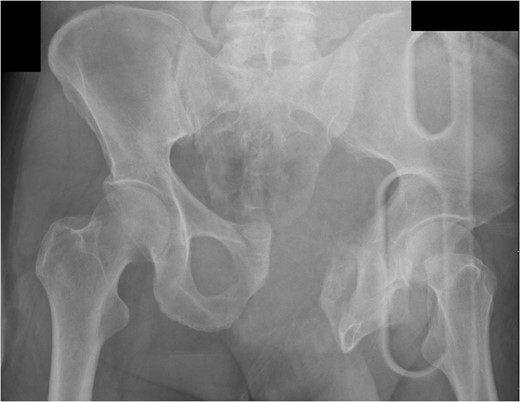

A 55-year-old male arrived at the ER, a large tree having fallen across his pelvis. The patient was hypotensive at the scene. He received over 1500 ml of crystalloid in route to the emergency room. Upon arrival to St. Mary’s Medical Center, the patient had a systolic pressure of 70. His heart rate was in the 130 s. The patient was awake and alert. A left subclavian central line was placed and he was transfused with two units of O-blood. The patient’s abdomen was soft and nontender. The patient had blood at his meatus. The patient’s pelvis was tender to palpation. His left leg was cold, mottled and pulseless. There was no femoral pulse on the left side. The chest x-ray was normal, however, the pelvis film revealed extreme widening and displacement of the symphysis pubis (Fig. 1). A bedsheet was wrapped around the patient’s pelvis and another two units of O-packed red blood cells were administered. Additionally, he was given four units of fresh frozen plasma. The patient was started on norepinephrine to control his persistent hypotension. His systolic blood pressure rose into the mid-90s and the patient was taken to the CT scanner. The CT scan revealed that the patient had an acute occlusion of his left iliac artery, as well as a large left iliac wing fracture with a massive associated hematoma. A right iliac wing fracture was located near the sacroiliac joint. There was pubic diastasis, as well as a left superior rami fracture with a modest associated hematoma. There was no extravasation of dye (Figs 2 and 3). The patient was taken directly to the operating room because he was developing significant abdominal distention in the face of continued hypotension. Anesthesiologists placed a second large-bore central line for fluid resuscitation. An exploratory laparotomy was performed, revealing an intraperitoneal bladder rupture. The patient was bleeding freely from his pelvic hematoma. Multiple attempts were made to pack the pelvis tightly with laparotomy pads, but efforts were unsuccessful. Because of the distorted anatomy obtaining proximal and distal control of the iliacs was extremely difficult. The patient suffered massive retroperitoneal venous bleeding, which we were unable to control. The patient exsanguinated on the operating room table; despite having received over 30 units of packed red blood cells, 30 units of fresh frozen plasma, several 10 packs of platelets, cryoprecipitate and factor VII A.

Pelvic fractures were categorized by Burgess and Young in 1990 [1]. Presenting with a very wide pubic symphysis, as well as a fracture of the iliac wing posteriorly, it appeared that this patient had an APC-III type fracture. These fractures are associated with nerve damage, organ injuries and significant bleeding [2].